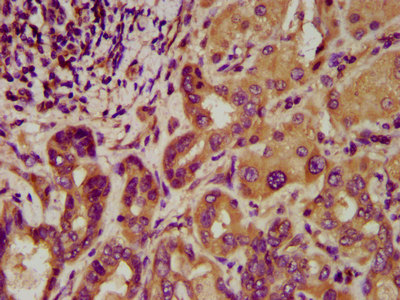

IHC image of CSB-PA818678LA01HU diluted at 1:200 and staining in paraffin-embedded human lung cancer performed on a Leica BondTM system. After dewaxing and hydration, antigen retrieval was mediated by high pressure in a citrate buffer (pH 6.0). Section was blocked with 10% normal goat serum 30min at RT. Then primary antibody (1% BSA) was incubated at 4°C overnight. The primary is detected by a biotinylated secondary antibody and visualized using an HRP conjugated SP system.